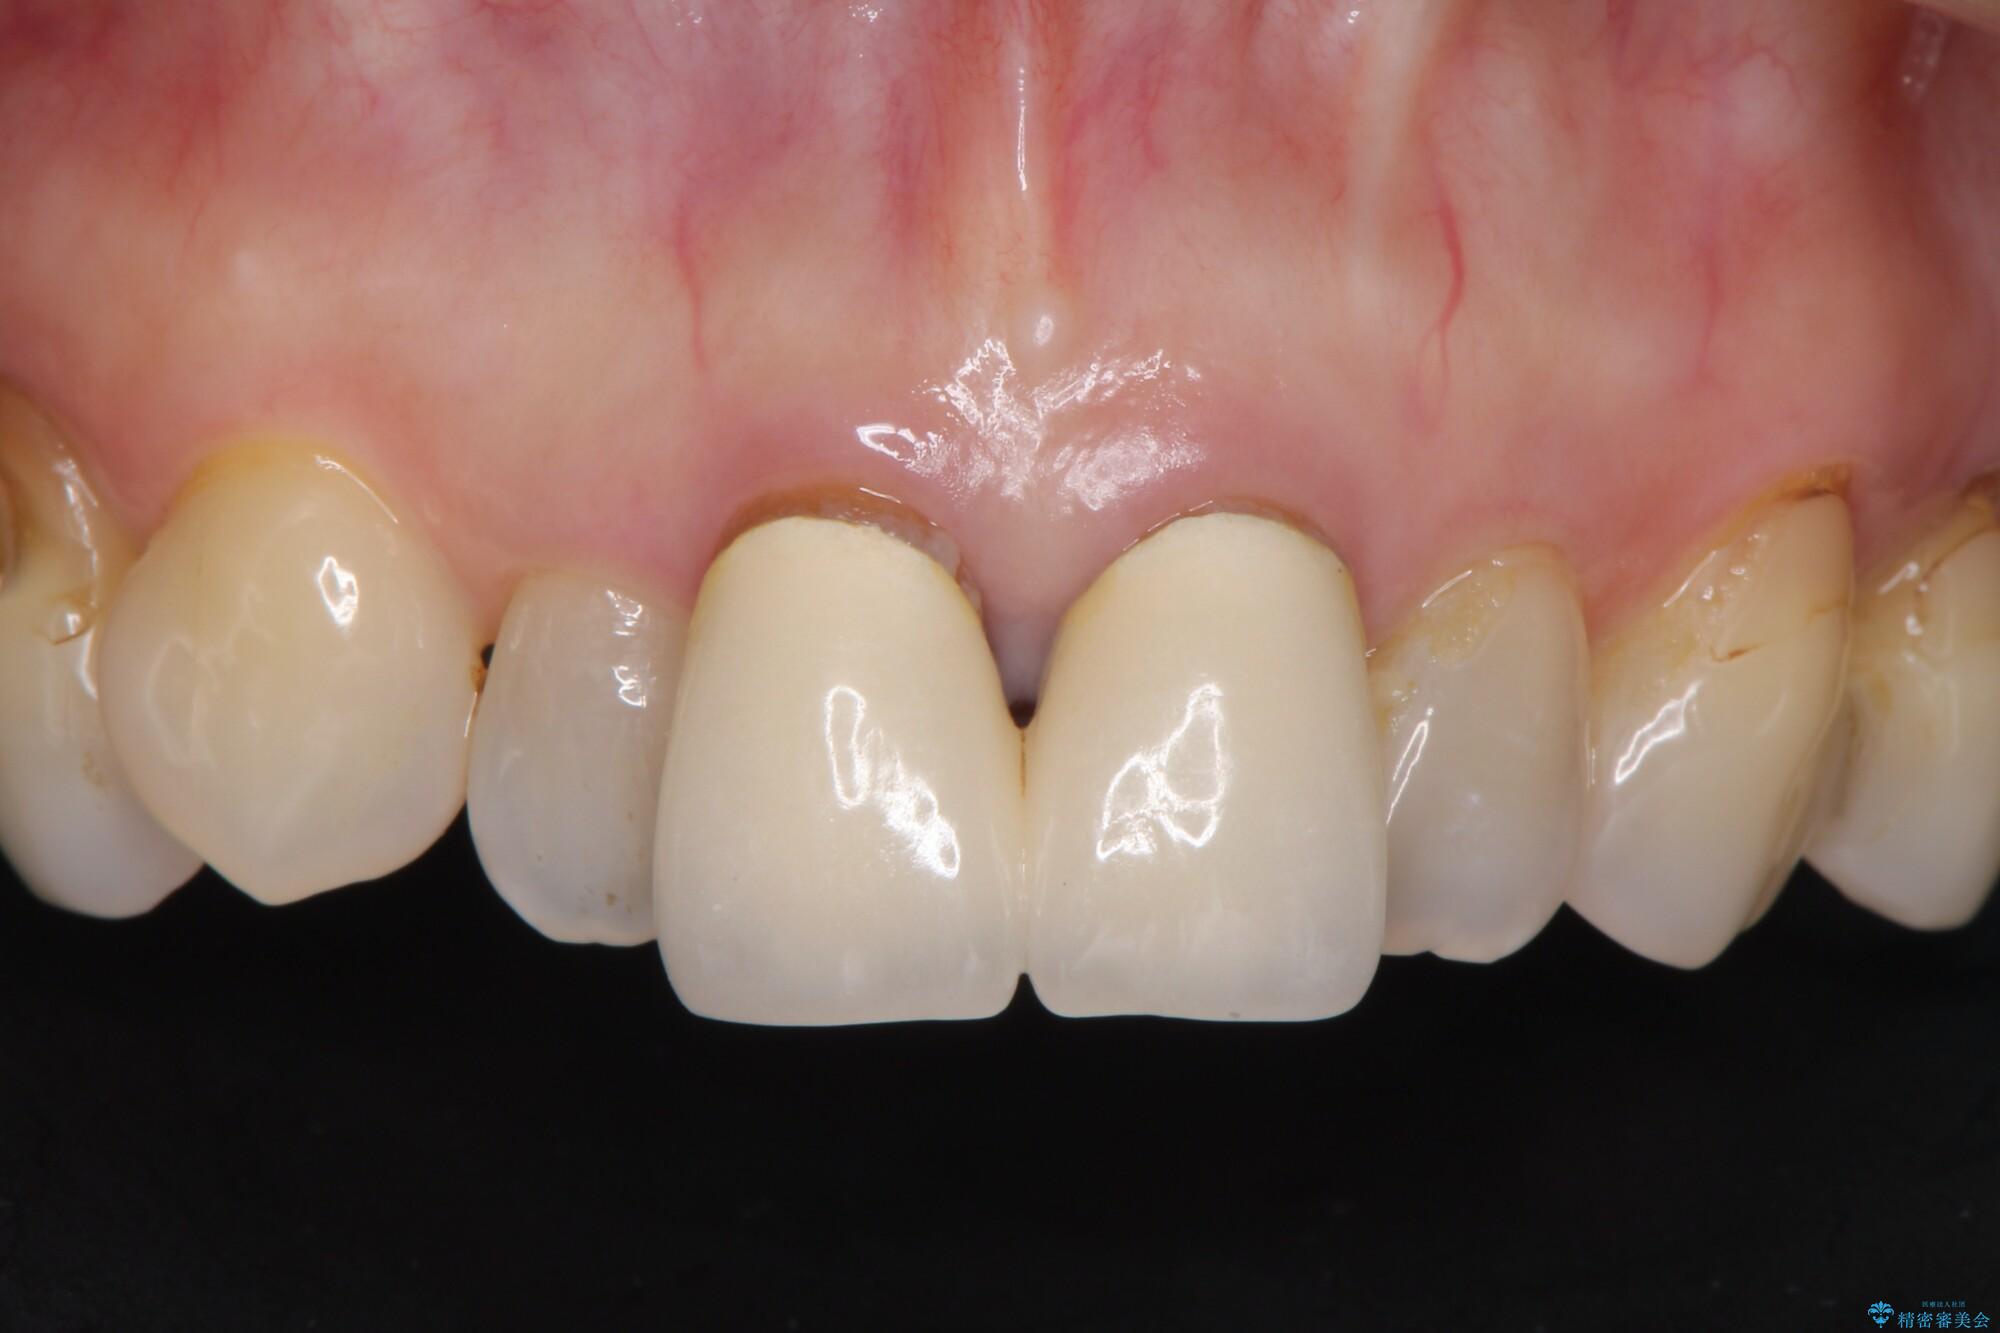

黒ずみもなくなり、自然な色味で大変ご満足いただけました。